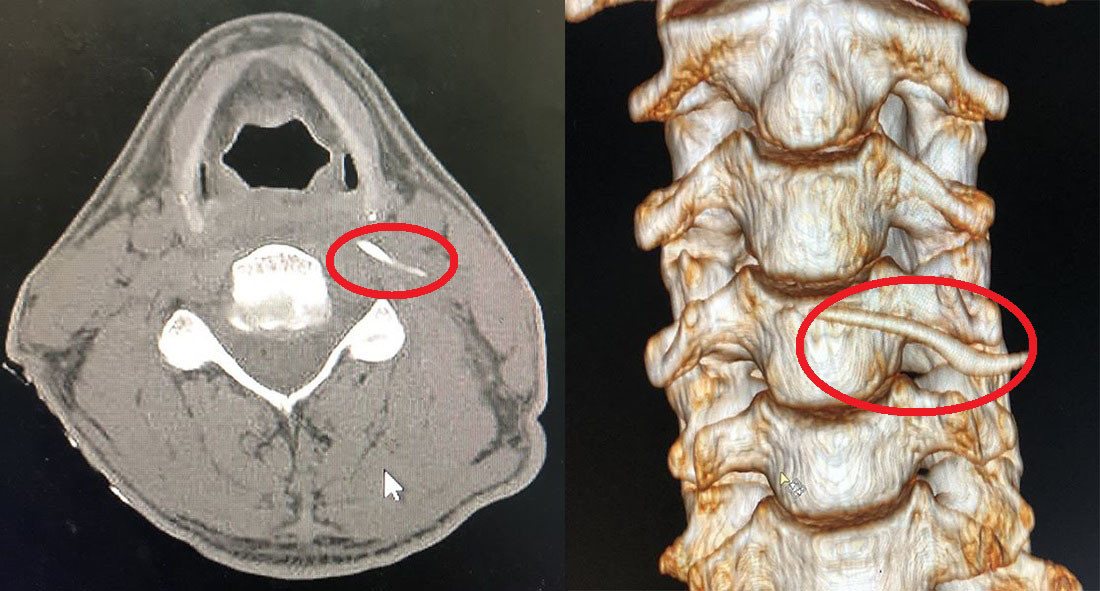

| Hình ảnh cắt lớp vi tính và Xquang xương cá trong cổ anh Nam. Ảnh: Vietnamnet |

Tại khoa Tai Mũi Họng, BV Hữu nghị Đa khoa Nghệ An, qua hình ảnh chụp cắt lớp vi tính và X-quang, các bác sĩ phát hiện chiếc xương sắc nhọn dài gần 4 cm đâm sâu vào vị trí thành sau hầu thanh quản, nằm trong khoang cạnh hầu và ngang mức bờ trên sụn giáp, sát cột sống cổ và miệng thực quản.